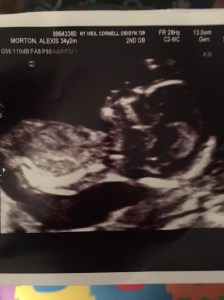

I had my anatomy scan! Baby looks great and although I feel enormous the baby is measuring average size.

Baby wasn’t super cooperative so I’m going back to finish the scan tomorrow.